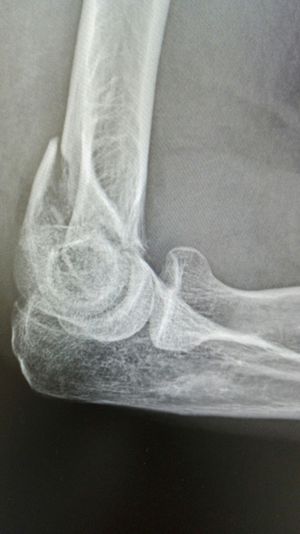

Xray

Fracture

Elbow

Supracondyle fracture